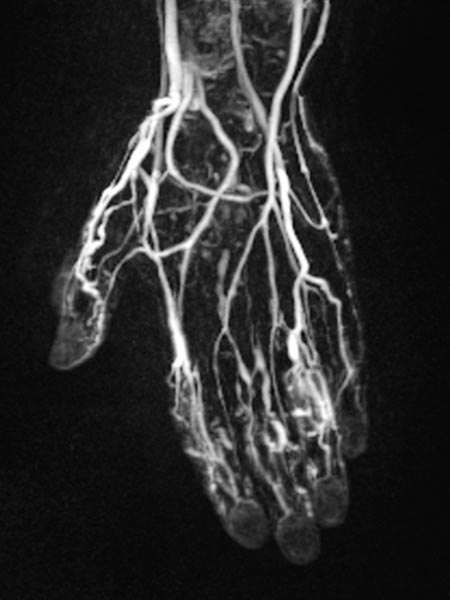

Dynamic, contrast-enhanced MR angiography of the hand, 30 s after intravenous contrast injection.

Normal hand arteries, no fast-flow situation, no dilated arteries or arteriovenous shunts are demonstrated.

Dynamic, contrast-enhanced MR angiography of the hand, 35 s after contrast injection.

Already in this early arterial phase, first enhancement of parts of the malformation via small arteriovenous fistulas (AVF) mainly in thumb, index finger and ring finger.

Dynamic, contrast-enhanced MR angiography of the hand, 67 s after contrast injection.

In this venous phase, slow pooling of contrast within the venous malformation.